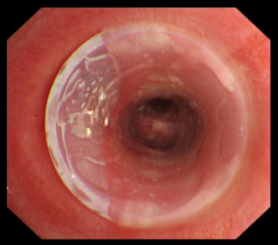

近年来,贵州航天医院各科室紧跟医学前沿,不断强技术、补短板,大力开展新技术、新项目,完成了许多高精尖、高难度、本地区“首例”的技术,填补了医院医疗技术空白,满足了群众日益增长的医疗需求。 贵州航天医院呼吸与危重症医学科是贵州省内呼吸疾病治疗规模最大,诊疗项目最全的呼吸疾病品牌科室,呼吸介入技术达到了全国先进水平,在贵州省内处于领先的地位。 本期,我们将为大家带来呼吸与危重症医学科特色技术——气道支架置入技术治疗呼吸不畅(已纳入乙类医保报销)。 案例分享 一患者因出现呼吸困难、气急等症状,听说我院呼吸与危重症医学科呼吸系统疾病诊疗实力在省内属于前列,慕名前来就诊,入院后,呼吸与危重症医学科为患者完善了胸部CT检查,提示:左主支气管肿瘤生长至气管下段,左肺不张,对此,科室立即组织多学科(MDT)讨论,对患者进行全面的诊断评估,诊断为:左肺鳞癌,左肺不张,气管下段内生型狭窄,左主支气管堵塞。 在充分了解患者及家属的治疗需求和征得治疗同意后,为进一步减轻患者呼吸困难症状,决定为患者实施气道支架置入技术,通过将支气管镜插入到气管中,使用气道球囊扩张器对狭窄的气道进行扩张,在病变部位置入支架扩张狭窄的支气管后,患者安全返回病房。 国产镍钛记忆合金支架植入步骤 术后,患者左主支气管通畅。 什么是气道支架置入技术 气道支架置入技术是一种用于治疗气道狭窄及气道相关性瘘等疾病重要的手段,尤其适用于因恶性肿瘤或其他原因导致的呼吸困难患者。是利用一种保持管腔完整性的人造装置——支架并应用支架置入器在X线透视或支气管镜直视下将支架置入气道保持气道通气功能的一种方法。 目前气道支架最常见的类型有可膨胀金属气道支架、硅酮支架及混合性支架等,以可膨胀金属支架为最常用。 气道支架置入技术原理 是将具有一定张力和弹力的支撑物(即气管支架)置入气道内,将狭窄或塌陷的气道撑开,从而维持气道通畅,或堵住破裂的瘘口。根据气管、支气管不同部位的解剖特点和病变情况,选择对应型号的支架,并通过气管镜的指引,在病灶位置植入合适的支架,也可根据气道的收缩性、不规则性和狭窄程度,进行适当调整。 气道支架置入技术优势 (一)快速缓解呼吸困难:支架置入能够迅速撑开狭窄或塌陷的气道,显著改善患者的呼吸困难症状。 (二)降低气道塌陷风险:对于某些肿瘤或炎症引起的气道狭窄,支架置入可以稳定气道结构,降低气道塌陷和窒息的风险。 (三)创伤小、恢复快:相较于传统手术,气道支架置入术具有微创的特点,患者术后恢复较快,痛苦较小。 气道支架可减轻或抵抗外部压力,扩大狭窄气道后,中央气道梗阻的症状和体征可立即减轻或消除,肺功能、运动能力及生活质量也得到改善。理想的气道支架应具备对气道壁物理性刺激小、置入后不移位、能阻止肿瘤或组织向支架内生长、不影响排痰、可以并容易回收等特点。 贵州航天医院 呼吸与危重症医学科专家团队 廖江荣 国务院政府特殊津贴专家 二级教授 主任医师 贵州航天医院副院长 国家级学术任职: 第二届中国医药教育协会介入微创专业委员会呼吸分会副主任委员 中国抗癌协会肿瘤微创治疗专业委员会常务委员 中国防痨协会结核病转化医学专业分会常务委员 第一届中国人体健康科技促进会呼吸介入专委会常务委员 中国医疗保健国际交流促进会结核病学分会第三届委员会常务委员 中国抗癌协会肿瘤微创治疗专业委员会粒子治疗学组第四届委员会委员 中华医学会结核临床专业委员会内镜介入委员 中华医学会放射学分会第十五届委员会介入学组呼吸系统介入专业委员会委员 北京健康促进会中青年专家委员会胸部疾病精准活检分委会副主任委员 中国医师协会介入医师分会第二届委员会肿瘤消融专业委员会委员 中国结核病防治综合质量控制专家指导委员会委员 亚洲冷冻治疗学会常务委员 世界内镜医师协会呼吸内镜协会常务理事 内镜临床诊疗质量评价专家委员会委员 “西部呼吸介入联盟”副理事长 专业擅长: 呼吸系统(肺)疑难病的诊断及危重病的抢救,呼吸系统(肺)感染性、疑难性疾病介入快速诊断(ROSE),尤其在肺癌、肺小结节早期诊断,肺癌微创综合靶向治疗,难治性、复治性、重症肺结核诊疗,硬质支气管下复杂性气道狭窄诊治,纤支镜介入治疗气道肿瘤、结核、气道狭窄(球囊扩张、支架植入、高频电刀、氩气刀、冷冻、灌洗、注药、微波消融),间质性肺疾病的诊疗上具有极高水平;带领团队勇于创新,在贵州省率先开展多项新技术、新疗法,如CT引导下及纤支镜下I125粒子植入及CT引导下微波、射频消融介入治疗肺癌等多项新技术,带动了贵州省肺部疾病的介入治疗水平提高。 蒋 婷 呼吸与危重症医学科 总负责人 副主任医师 专业擅长:从医20余年,在呼吸系统疾病、介入呼吸病学、肺部结核、肺部肿瘤等方面具有丰富的临床经验和专业技能,尤其是慢性阻塞性肺疾病、支气管扩张、肺结核、耐药肺结核、肺癌、胸腔积液等肺部疾病的诊治、微创介入、危重病患者抢救。 现任中国防痨协会人兽共患结核病专业分会委员,中国女医师协会第一届介入专业委员会委员,贵州省基层呼吸疾病防治联盟-间质性肺疾病联盟委员,贵州省防痨协会第七届理事会理事,贵州省中西医结合学会呼吸专业委员介入呼吸病学组委员,贵州省遵义市中医药学会中西医结合肺病(呼吸)分会副主任委员,贵州省遵义市中医药学会中医肿瘤专业委员会常委;发表论文数篇,参与并主持多项科研项目。 李桂凤 呼吸与危重症医学科 三病区 主任 副主任医师 专业擅长:从事呼吸系统疾病、结核病学、介入呼吸病学、肿瘤综合治疗、呼吸康复等临床工作20余年,擅长呼吸内科常见病、多发病及疑难重症危重病症的诊治,尤其对重症疑难结核及耐药结核病、介入治疗(肺)呼吸系统疾病、呼吸危重病抢救等方面具有较高诊疗水平。 中国防痨协会非结核病专业委员会委员,贵州省中西医结合学会第六届呼吸专业委员会委员,贵州省康复学会睡眠障碍康复专业委员会委员,遵义市呼吸内科医疗质量控制中心委员,遵义市落实民生实事结核病筛查阅片专家组成员;主持及参与实用新型专利3项。 周裕祥 呼吸与危重症医学科 四病区 主任 副主任医师 专业擅长:经皮肺介入、经血管介入诊疗技术。 贵州省中西医结合学会呼吸专业委员会介入呼吸病学组常务委员,中国医师协会呼吸医师分会介入呼吸病学工作委员会呼吸病血管介入学组委员,贵州省中西医结合学会呼吸学分会委员,遵义市医学会放射肿瘤治疗学分会委员,中国医药教育协会介入微创呼吸分会委员,北京健康促进会中青年专家委员会胸部疾病精准活检分委会委员;曾赴重庆医科大学RICU、珠海市人民医院介入科进修学习。 杨 芳 呼吸与危重症医学科 内镜中心 主任 副主任医师 专业擅长:从事临床工作约16年,对呼吸危重病的救治有独到的见解,尤其擅长呼吸系统疾病的介入诊疗,对呼吸内镜下的诊治及经皮肺穿刺诊疗技术具有丰富的临床经验。 亚洲冷冻治疗学会委员,中国医药教育协会介入微创呼吸分会委员,西南结核病医院联盟第二届委员会秘书/委员,贵州省中西医结合学会第六届呼吸科专业委员会委员,贵州省中西医结合学会呼吸专业委员会介入呼吸病学组秘书,贵州省中西医结合学会呼吸专业委员会基层康复学组副组长,贵州水利电力医学科学技术会高原医学分会委员,遵义市中医院学会中西医结合肺病(呼吸)分会秘书/常务委员,遵义市医学会肿瘤学分会(第二届)委员,遵义市医学会放射肿瘤治疗学分会第二届委员;主持及参与科研课题多项,参编著作《呼吸内镜操作技术规范》、《介入结核病学》,发表论文数篇。 贵州航天医院 呼吸与危重症医学科专家团队 贵州航天医院呼吸与危重症医学科以呼吸危重症和介入呼吸病学为强力推手,以肺部感染性疾病及肺癌、肺小结节的早期精准诊疗、慢性呼吸疾病康复治疗为特色,以人才团队建设为核心的科室发展模式,现已成为省内呼吸疾病治疗规模最大,诊疗项目最全的呼吸疾病品牌科室。是贵州省医学重点学科、临床医学重点专科建设单位,遵义市首批呼吸重点学科、重点专科建设单位。是国家卫健委能力建设和继续教育肿瘤微创介入建设中心、贵州省县级医院微创介入培训中心、遵义市呼吸疾病临床医学中心。是国家呼吸医疗质量控制与管理哨点医院、遵义市呼吸内科专业医疗质量控制中心。是中国医药教育协会介入微创呼吸分会呼吸介入技术培训中心单位;国家卫健委海医会呼吸分会ROSE专委会“诊断性介入肺脏病学快速现场评价”培训基地;中国肺癌防治联盟“贵州航天医院肺结节诊治”分中心,中国人体健康科技促进会呼吸介入技术培训基地,贵州省中西医结合会呼吸学分会呼吸介入专委会主委单位。 基本情况 平均每年开展气管镜诊疗约4000例,经皮肺穿刺介入诊疗近千例,开展的项目包括经支气管镜(软、硬)下冷冻、氩气刀、高频电刀、球囊扩张、支架置入、超声内镜诊疗等气道介入诊疗技术,经皮肺穿刺活检及肿瘤消融术(微波、冷冻)、ROSE技术、内科胸腔镜诊疗及经血管介入诊疗技术,且多项呼吸介入诊疗技术在省内处于领先水平。 诊疗范围 致力于呼吸系统感染性、疑难性疾病的介入快速精准诊疗;肺癌与肺小结节早期精准诊疗水平项目提升。擅长于呼吸系统(肺)疑难病的诊断及危重病的救治,尤其在肺癌、肺小结节的早期诊断;肺癌综合靶向治疗;肺结核综合诊疗;肺部疾病的介入诊疗在省内处于前沿水平。